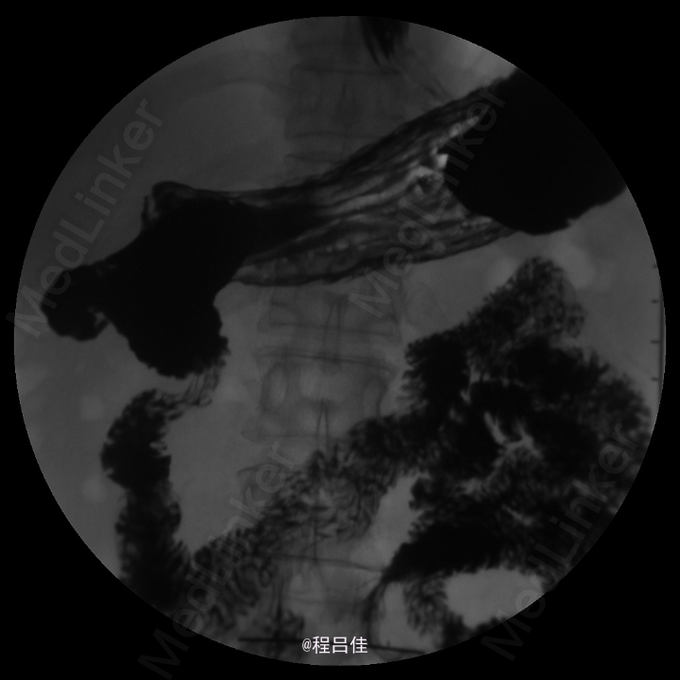

查体:T 36.4℃,P 80次/分,R 13次/分,BP 110/78mmHg。心肺腹阴性。 辅查: 常规胸透示食管:对比剂通过顺畅;食管胃环上提,并可见一浅切迹影,膈上见胃黏膜影,立位时消失。余食管未见明确狭窄、扩张现象,管壁光整,柔软,舒缩功能良好,黏膜皱襞排列规则,未见明确增粗、紊乱、中断现象,未见明确龛影及充盈缺损影;可见少量胃食管返流;球后部扩张,黏膜增粗,扩张以下肠管稍狭窄,但肠壁黏膜规整、柔软,未见明确充盈缺损。结论1.考虑滑动性食管裂孔疝。 2.十二指肠球后部局部稍变窄,黏膜增粗,建议进一步肠镜检查。 3.轻度胃食管返流。